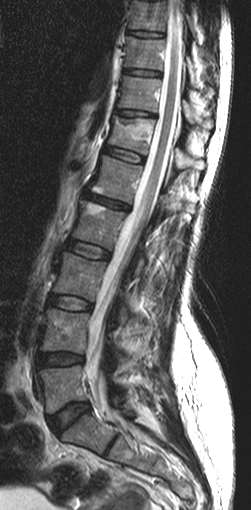

• In spinal truma CT is useful for localization of bone fragments, while MRI can visualize soft tissue structures within the spinal canal and discoligamentous injuries..

3.Back pain and decreased anal sphincter tone after motor accident. Left panel: Acute fracture of the 12th thoracic vertebra on CT. Right panel: Edema as a sign of acute fracture in the 12th thoracic vertebra on sagittal T2WI.